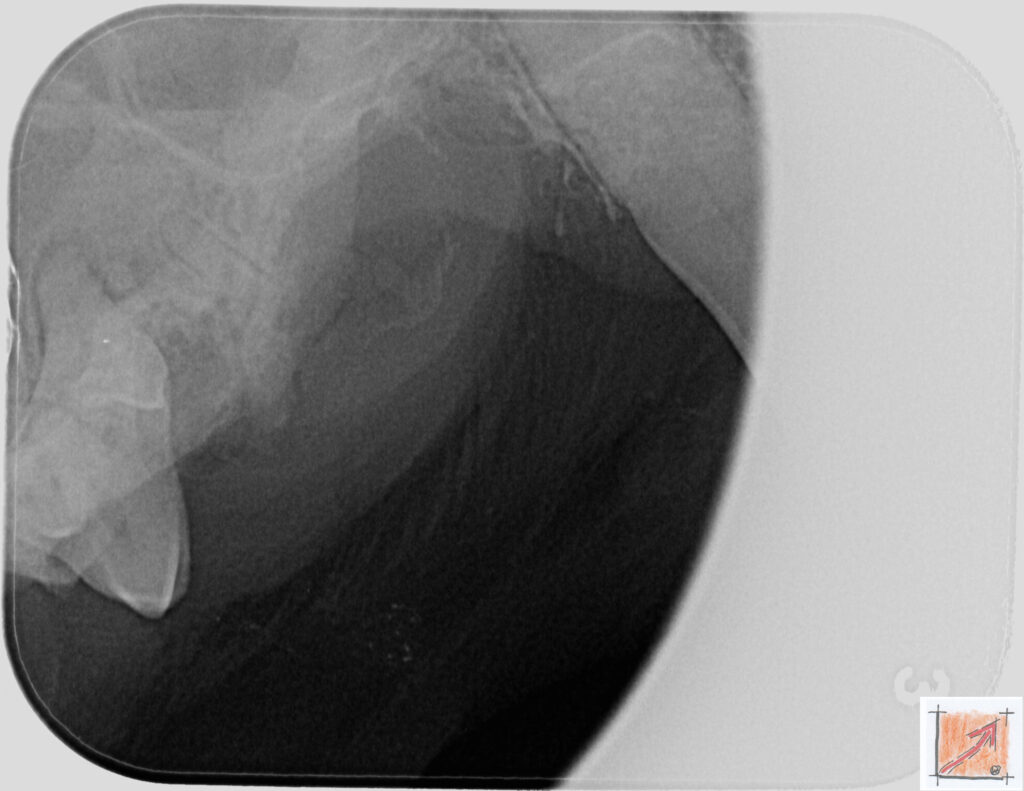

Röntgenbilder vom Thierrischen Orakel bei der Zahn-OP:

Warum Dentalröntgen beim Chihuahua lebenswichtig ist:

Ein Blick hinter die Kulissen von Chihuahua-Zähnen:

In dieser Galerie zeigen wir exklusive intraorale Röntgenaufnahmen einer Zahn-Operation beim Thierrischen Orakel als Chihuahua vom BauFachForum. Während oberflächlicher Zahnstein oft sichtbar ist, verbirgt sich die wahre Gefahr für das Herz meist unter dem Zahnfleischsaum.

Das digitale Dentalröntgen ist der Goldstandard in der modernen Tiermedizin, um parodontale Entzündungsherde und Wurzelabszesse sicher zu diagnostizieren. Für Chihuahuas wie dem Thierrischen Orakel, mit Mitralklappeninsuffizienz ist dieser diagnostische Schritt essenziell. Nur wenn versteckte Bakterienherde an der Zahnwurzel oder mit dem Fachbegriff Apikalabszesse erkannt und saniert werden, kann das Risiko einer bakteriellen Endokarditis oder einfach ausgedrückt einer Herzinnenhautentzündung minimiert werden.

Unsere Aufnahmen von Patienten dem Thierrischen Orakel verdeutlichen den Unterschied zwischen einer rein optischen Zahnreinigung und einer medizinisch fundierten Sanierung unter Röntgenkontrolle.

Chihuahua Mitralklappeninsuffizienz Trachealkollaps:

Wichtig ist im Vorfeld die Zahnhygiene des Chihuahuas. Die Bilder zeigen Dentale Röntgenbilder vom Thierrischen Orakel als Chihuahua-Hund während seiner Zahn-OP. Darstellung von Kieferknochen und Zahnwurzeln zur Diagnose von Parodontitis.

Zahnröntgenaufnahme bei Chihuahua Thierry:

Untersuchung der Zahnwurzeln auf Entzündungsherde als Prophylaxe gegen bakterielle Endokarditis.

Intraorales Dentalröntgen eines Chihuahuas:

Die Bilder zeigen Zähne und Wurzelstrukturen im Unterkiefer zur Planung einer Extraktion bei hochgradigem Zahnstein.